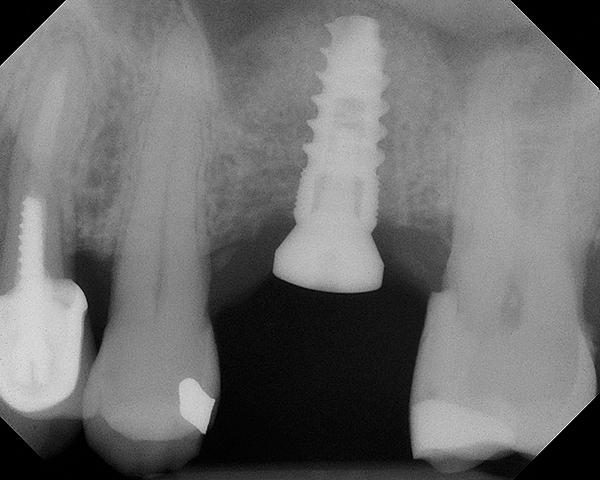

The implant is then delivered and should be well stabilized in the bone. If there is any mobility of the implant, it can either be placed a little deeper (if there is enough native bone) or the implant can be removed and the procedure aborted, in which case it would be a two-stage procedure. This should rarely occur with the tapered designed implant, even with only 2 mm of native bone. Using a bone-level platform-shifting implant (or a tissue-level designed implant) is critical, as the hard and soft tissue will establish a biologic width. If an external hex type of implant is used and the shoulder is placed at the bone level, an expected bone loss of 1.5 mm to 2 mm will occur.24 Figure 10 shows proper bone-level implant depth placement with a platform-shifting design. In this case, a 3-mm healing abutment was placed at the time of surgery to avoid a secondary uncovering surgery, but an implant-level healing abutment could have been placed instead. As can be seen, there was only about 2 mm to 3 mm of native bone height. The membrane was raised about 8 mm to 9 mm. Comparing the radiograph on the day of surgery (Figure 10) to the 6-month postoperative radiograph (Figure 11) shows no loss of native bone, as well as the positive change in appearance of the grafted bone. The 3.5-month CBCT scan (Figure 12) shows good healing of the bone with no coronal bone loss. With minimal native bone present, as in this case, the use of a non-platform-shifting or non-tissue-level implant design could be problematic. After 1.5 mm to 2 mm of crestal bone loss, an external hex designed implant could develop instability with possible implant failure. If a non-tapered implant is used and bone loss occurs during healing, migration of the implant into the sinus could potentially occur. The surgeon can use either a healing abutment or implant-level closure screw over the implant shoulder. With patients who tend to use their tongues to explore or play with the area, or if the area is under a removable partial denture, a closure screw is recommended.

Fig 10. Radiograph of implant No. 3 and sinus augmentation, day of placement. There is about 2 mm to 3 mm of native bone, and the sinus has been raised about 8 mm to 9 mm.

Figure 10

Fig 11. 7-month postoperative radiograph of the restored implant No. 3.

Figure 11

Fig 12. CBCT scan (Kodak 9000D) showing 3.5-month postoperative of implant No. 3 in place. Note homogenous appearance of the bone.

Figure 12